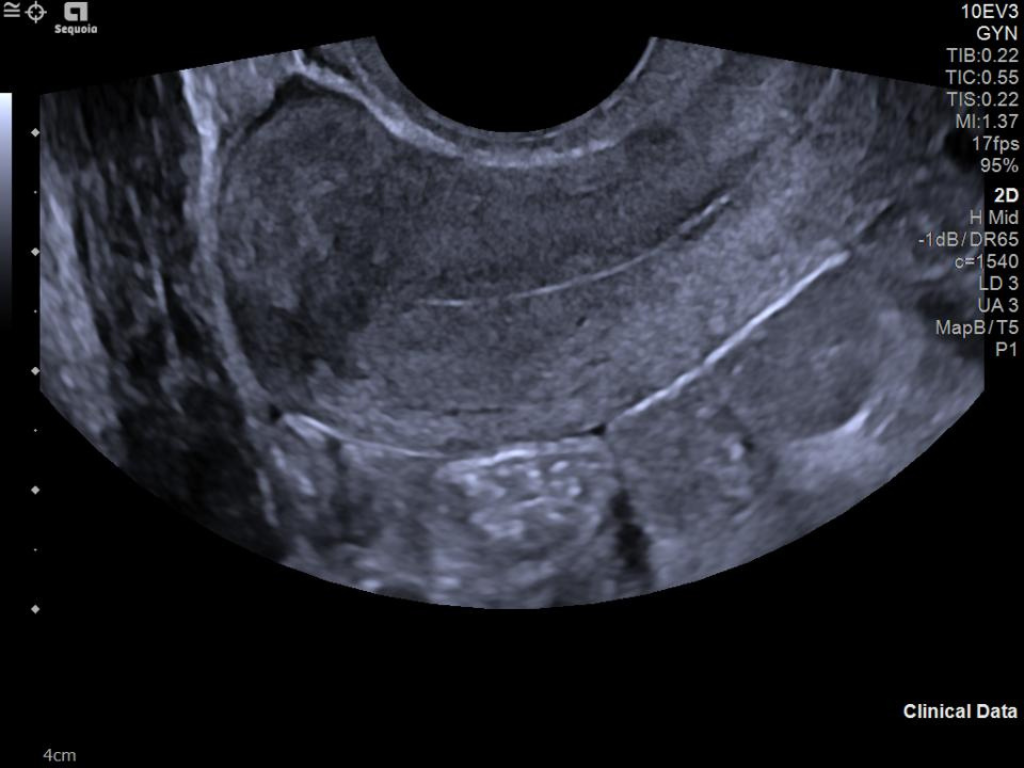

The ACUSON Sequoia is an advanced diagnostic tool that integrates cutting-edge technology and AI-powered applications to streamline diagnostic processes. This system is designed to cater to patient-specific needs, ensuring accuracy and efficiency in various clinical settings such as Radiology, OB/GYN, Shared Service and beyond.

The latest updates on ACUSON Sequoia use the power of groundbreaking AI for abdominal cases, includes advanced breast visualization to deliver new levels of image quality confidence, and tackles the toughest challenges in musculoskeletal imaging, all while saving your team from needless strain and pain.

ACUSON Sequoia’s InFocus imaging architecture eliminates the need for conventional focal zones to create a fully focused image faster than conventional systems. Our InFocus technology applies to all imaging transducers and exam types giving you consistent imaging across clinical segments. Some of the benefits are:

- Image uniformity throughout the field of view

- Aesthetically pleasing speckle

- Improved spatial and contrast resolution

- Clear near field to far field

- High resolution imaging at high frame rates